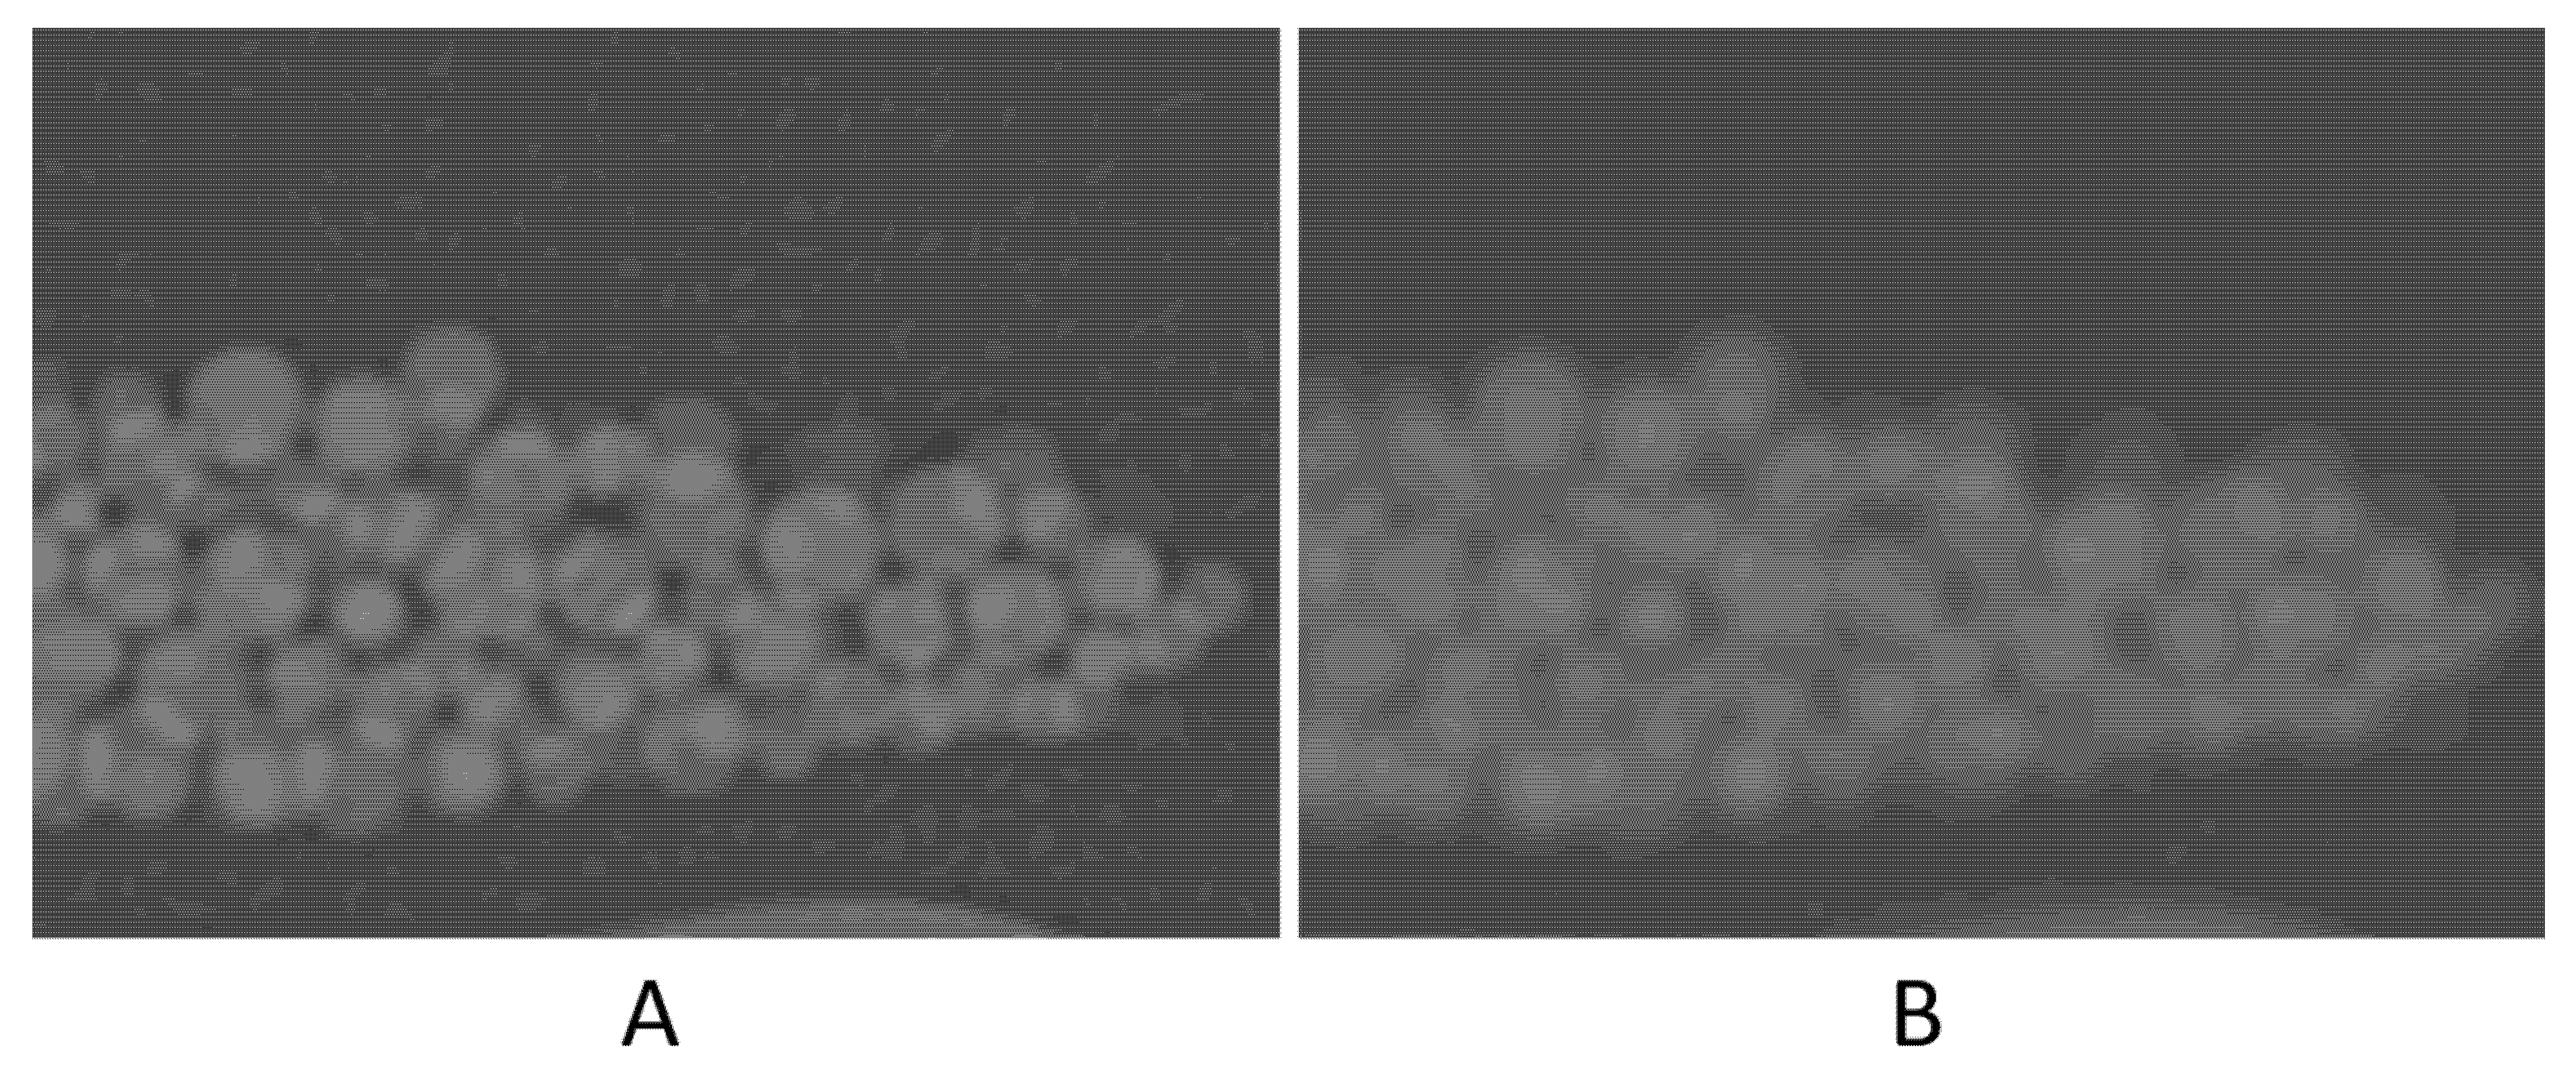

High noise level (four times higher than that of the original scan) seemed to have resulted in ~1% degradation in accuracy. The contrast-to-noise ratio (CNR) in the original scan is 50.8, as opposed to 12.1 in the high-noise scan. This 75% reduction in CNR, despite being large, had only a small (~1%) effect on the volume measurement accuracy. A noticeable decrease in accuracy was with the high-resolution (Lung) kernel; it changed to −6.2%. This kernel, like other edge-enhancing kernels, uses algorithms that alter CT numbers and noise texture in a non-uniform manner to preserve the high-resolution structures of the image23. Figure 5 shows the difference in the image appearance of a standard versus Lung kernels. The high-density variation in both the background (petroleum jelly) and beads is likely the cause of the relatively high error.

Figure 5.

Zoomed-in images to compare the image appearance with Lung filter (A) and standard filter (B).